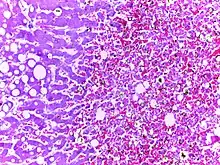

![]() | Dysgerminoma | Dysgerminoma characterized by uniform cells resembling primordial germ cells separated by fibrous septa with lymphocytes. | Category: Histopathology of ovarian dysgerminoma | Ovarian dysgerminoma |